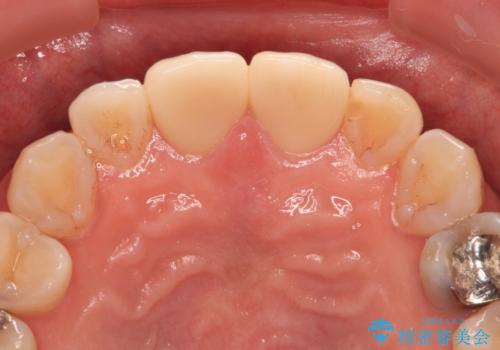

- つぎはぎのある前歯のセラミックの色合いが気になるとのことで来院された患者様です。

グレーの色が透けて見える気がする点が気になっていらっしゃり、やや黄色みのある色を希望されていました。

仮歯に置き換えた後にオールセラミッククラウンにて補綴治療を行うこととしました。